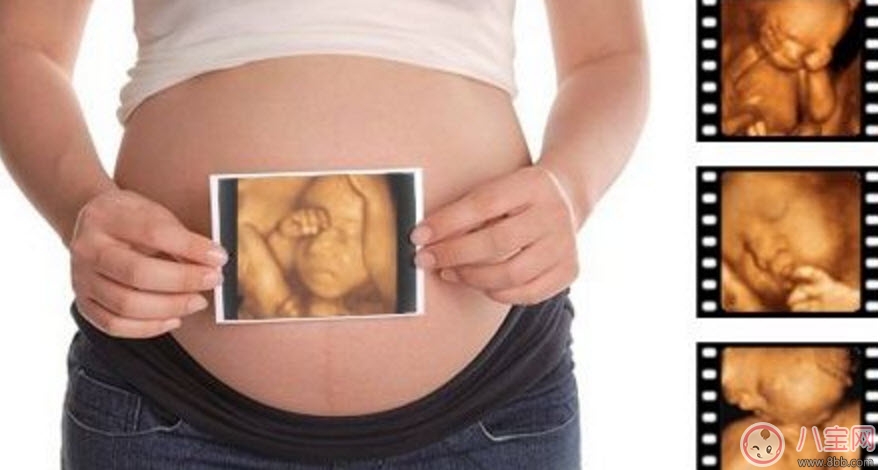

孕婦的羊水適量的話就可以做這項檢查。但是受胎兒體位、胎盤以及孕期不同等方面的因素影響,專家建議最佳做四維彩超的時間應該是12-30周,這個時期就可以完全獲取到胎兒的面部以及身體等結構的圖像。懷孕十個月的時候里最少要做3次的四維彩超,時常觀察胎兒成長。

第一次檢查:選擇懷孕14周左右

選擇在懷孕4個月的時候做四維彩超檢查。在這個檢查過程中,可以觀察到胎兒的頭、體、以及四肢的整體圖像,觀察時,醫生也會特別注意胎兒的整體活動是否協調。協調的話表示胎兒生長的很健康,當然不協調的話也是可以接受治療改善的,這個時候還有時間。

第二次檢查:選擇懷孕22周左右

孕婦在懷孕5個多月的時候做四維彩超檢查。在觀察時,可以明顯的看到胎兒要比上次觀察的要大,而且在同一幅圖像上還不能完全地顯示出胎兒的全部結構。可以通過局部的觀察胎兒是否健全,有沒有一些其他癥狀的出現。如果真的這樣,胎兒很大的可能會是畸形生長的、發育明顯不健康。

第三次檢查:懷孕28周左右

懷孕7個月左右也是做四維彩超檢查的好時機。這個時期的胎兒的皮下脂肪、面部表情都會比較飽滿、清晰。同時還可以看到胎兒在母體中的形體動作以及面部表情。這個階段的檢查對于胎兒的發育是否正常可以更加明確。這對懷孕晚期的胎兒健康尤其重要,所以必須好好做詳細的檢查。